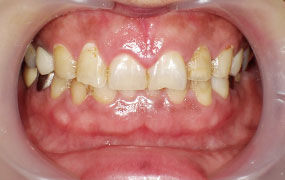

歯ぐきのホワイトニングと言われるガムピーリング - たとえば、タバコをよく吸う人はメラニン色素が沈着しやすく、歯ぐきの黒ずみが目立ちます。歯ぐきのホワイトニングといわれるガムピーリングは、そのような黒ずみを解消する治療法です。

黒ずみの原因は、メラニン色素によるもののほか、金属を使用した歯の治療などによっても起こります。

施術内容は簡単で特殊な薬剤を歯ぐきに塗るだけです。塗布後には歯ぐきに白い膜ができますが、1週間ほどでそれが剥がれます。膜とともに色素が剥がれ、本来の美しい歯ぐきの色を取り戻します。

施術前

施術中

施術後